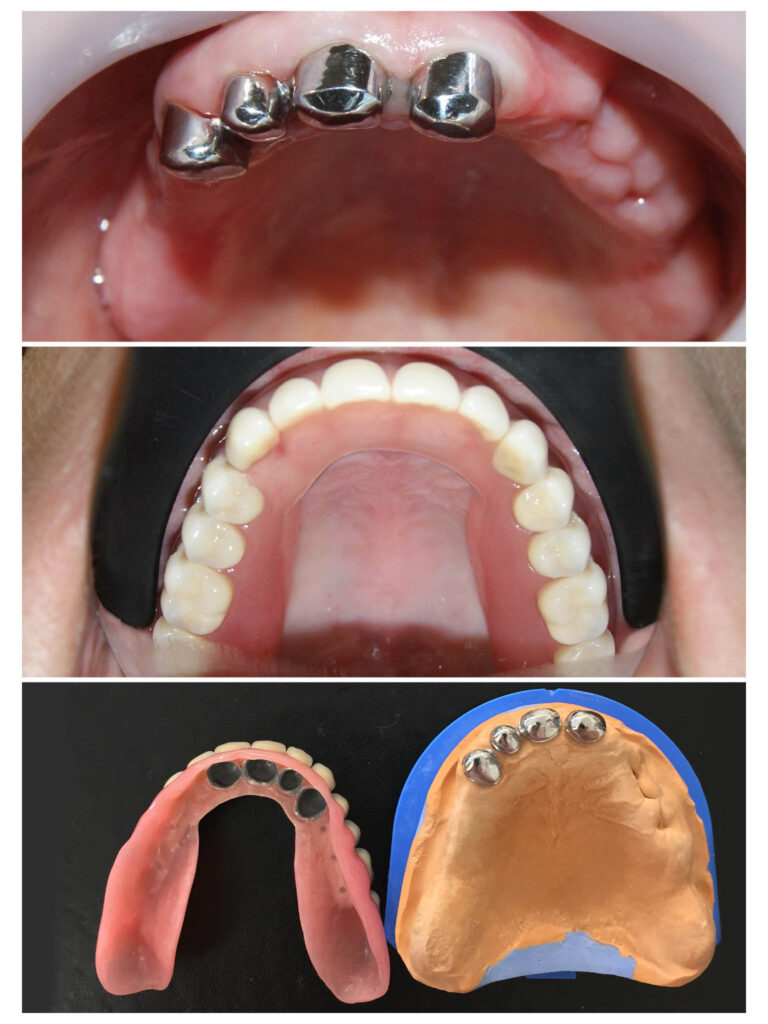

Proteza telescopată – stabilitate perfectă

Proteza telescopată  și proteză scheletată aplicate pe dinții tratați corect! Execuția riguroasă oferă stabilitate excelentă.